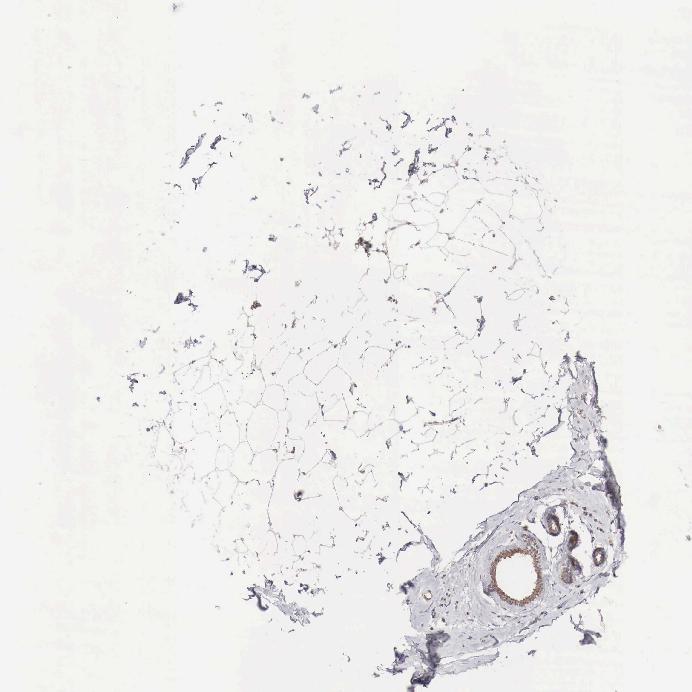

ADIPOSE TISSUE - Antibody stainingi

Antibody staining in the annotated cell types in the current human tissue is reported as not detected, low, medium, or high, based on conventional immunohistochemistry profiling in selected tissues. This score is based on the combination of the staining intensity and fraction of stained cells.

Each image is clickable and will lead to virtual microscopy that enables deeper exploration of all samples and also displays staining intensity scores, fraction scores and subcellular localization as well as patient and tissue information for each sample.

Antibody HPA000527

Adipocytes Not detected